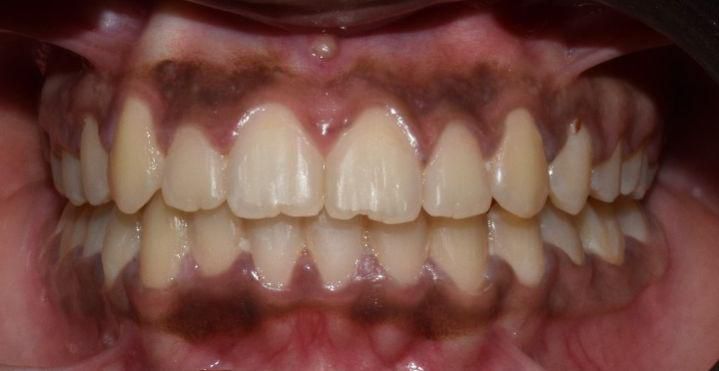

Before & After Results

At Aline Dent, we take pride in delivering visible and lasting improvements in our patients’ smiles. Our before-and-after results highlight the effectiveness of modern dental treatments combined with personalized care. This gallery showcases real dental cases treated at our clinic, giving you a clear idea of how different dental concerns can be corrected with the right treatment approach.

From minor corrections to complete smile enhancements, these teeth transformation results demonstrate how professional dental care can improve both oral health and appearance. Our experienced dental team carefully evaluates each patient’s needs and creates customized treatment plans to achieve natural, healthy, and confident smiles.

In this gallery, you will find a variety of smile makeover cases, including treatments for crooked teeth, gaps, discoloration, damaged teeth, and other common dental concerns.